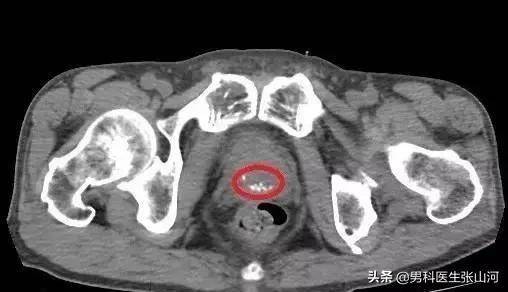

不少患者行前列腺B超时都会出现前列腺钙化灶的诊断,很多患者都不知道前列腺钙化灶是怎么回事,今天就给大家科普一下前列腺钙化灶是什么,有什么意义,怎么预防。

前列腺钙化灶其实是指在发生前列腺炎时,一些含钙物质(如磷酸钙等),与前列腺腺泡或腺管内的细菌、上皮细胞混合而形成的斑块。随着这些物质混合,斑块增大会阻塞腺泡及腺管,随着斑块增大,前列腺钙化灶可形成结石。

大部分前列腺钙化灶并没有症状,通常是在行B超检查时发现,所以一般也不需要特别处理。但是当前列腺钙化灶形成前列腺结石,会出现血尿、尿痛、尿频、尿急等症状,这时就需要手术治疗。